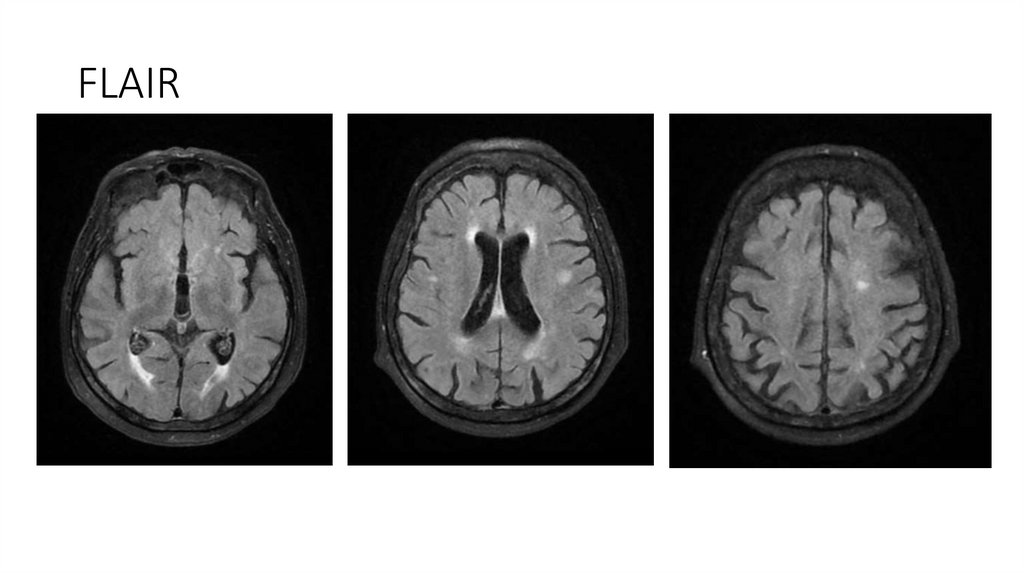

18. МРТ ГМ от 08.04.2025

Описание

-Срединные структуры не смещены.

-Желудочки обычной формы и размеров.

-Субарахноидальные пространства не расширены.

-Дифференциация серого и белого вещества сохранена.

-В белом веществе головного мозга, в паравентрикулярных и конвекситальных областях визуализируются множественные очаги

диаметрами 3-10мм, вероятно, сосудистого генеза.

-Отмечается незначительное расширение периваскулярных пространств.

-МР-сигнал от подкорковых ядер не изменен.

-Селлярная область без патологических изменений.

-Размеры гипофиза в пределах нормы.

-Стволовые структуры и мозжечок в пределах нормы.

-Мостомозжечковые углы без особенностей.

-Краниовертебральный переход не изменен.

-Придаточные пазухи и ячейки сосцевидных отростков воздушны.

-Содержимое глазниц без особенностей. ;

Заключение

• МР-картина множественных очагов в белом веществе головного мозга, вероятно,

сосудистого генеза.

21. FLAIR